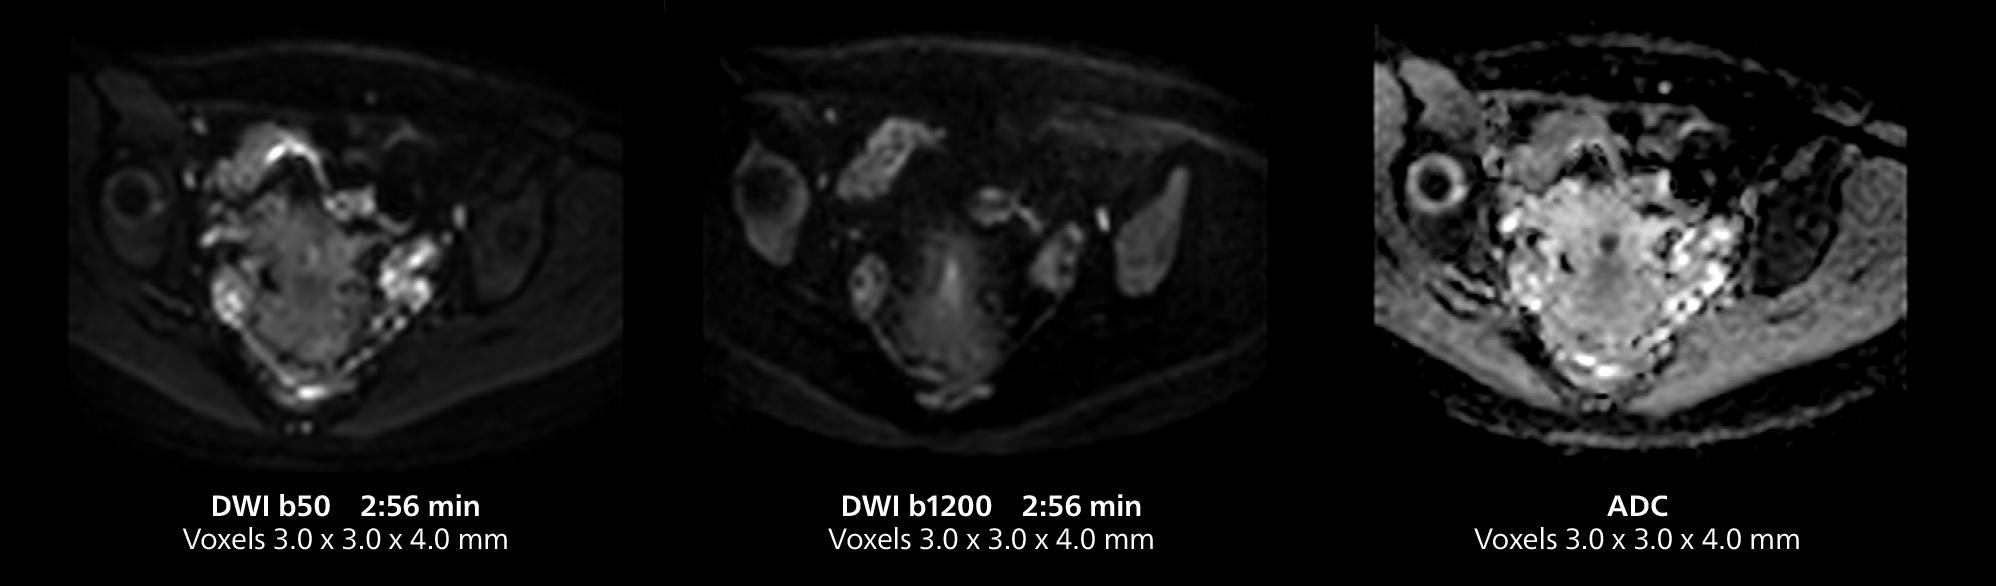

Dr. Gellée highlights the robust free-breathing scans as “the feature that makes the biggest difference in my daily work. The 3D free breathing sequences are very reproducible, and the axial acquisition is very good. For example, in endometriosis, which is one of my focus areas, it provides high contrast and good resolution so that I can see small details. We also use free breathing for liver and pancreas imaging. In multi-phase liver studies, 4D Free Breathing delivers 3-second temporal resolution, making a dynamic scan with more than one arterial phase possible.”

This MRI case illustrates imaging of salivary gland abnormalities with different sequences. Compressed SENSE allows to accelerate scanning while maintaining high quality. With mDIXON XD, different contrast types can be obtained from scanning one sequence.